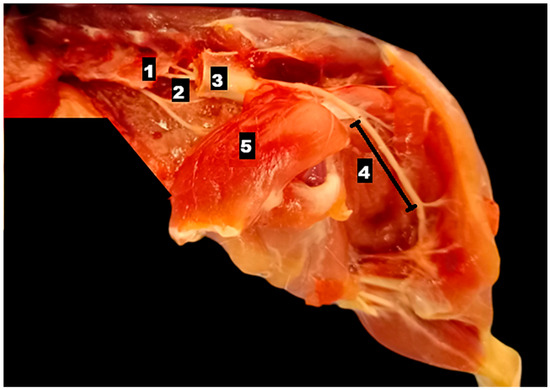

A 10-year-old castrated male Chihuahua weighing 3.06 kg was presented with a chronic, progressively worsening cough of five months’ duration. Diagnostic imaging, including thoracic radiography and computed tomography, identified a well-defined cranial mediastinal mass consistent with a thymic tumor. Surgical excision was performed via median sternotomy with complete thymectomy. Following tumor removal, sternal closure was achieved using a non-absorbable ultra-high-molecular-weight polyethylene (UHMWPE) suture material (FiberWire®, Arthrex, Naples, FL, USA). Histopathological examination confirmed the diagnosis of an epithelial-predominant thymoma with narrow but complete surgical margins. Postoperative recovery was uneventful, and the dog was discharged three days after surgery. Clinical signs, including coughing, progressively improved during follow-up. Radiographic evaluation performed up to postoperative day 57 demonstrated stable sternal alignment without evidence of dehiscence, implant-related complications, or disease recurrence. This report describes the first clinical case of FiberWire use for median sternotomy closure following thymectomy in a dog. The favorable clinical and radiographic outcomes observed during postoperative follow-up suggest that FiberWire may represent a viable alternative to traditional stainless-steel wire for sternal fixation in canine thoracic surgery. Full article